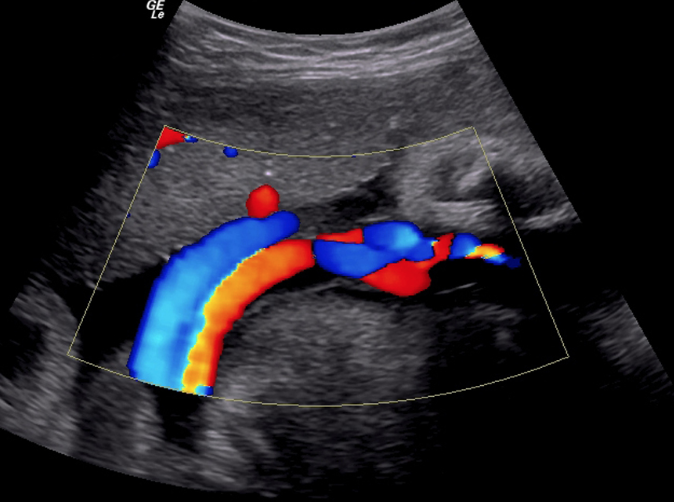

Actualmente la prueba ideal para el diagnóstico y seguimiento de estas lesiones es el eco-doppler, un estudio no invasivo y de alta fiabilidad.

El eco-doppler mide la velocidad de la sangre dentro de la arteria y las características de la placa.